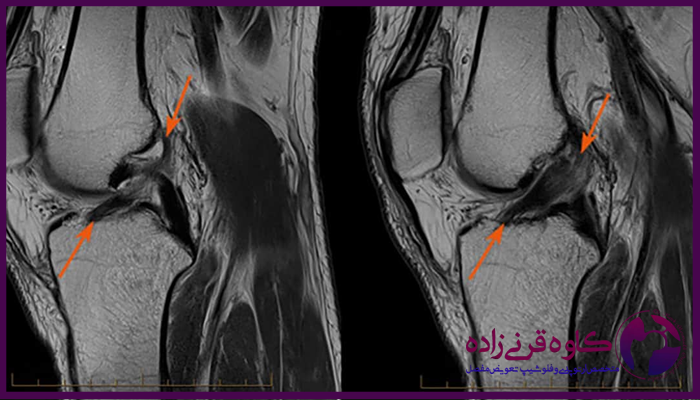

برای تایید تشخیص و بررسی شدت آسیب، معمولا از تصویربرداری به ویژه ام آر آی استفاده میشود که پارگی رباط ها و سایر آسیب ها را به طور دقیق نشان میدهد. در برخی موارد، آرتروسکوپی زانو نیز برای بررسی وضعیت داخلی زانو و تعیین روش درمانی مناسب مورد نیاز است.

عکس ام ار ای پارگی رباط زانو